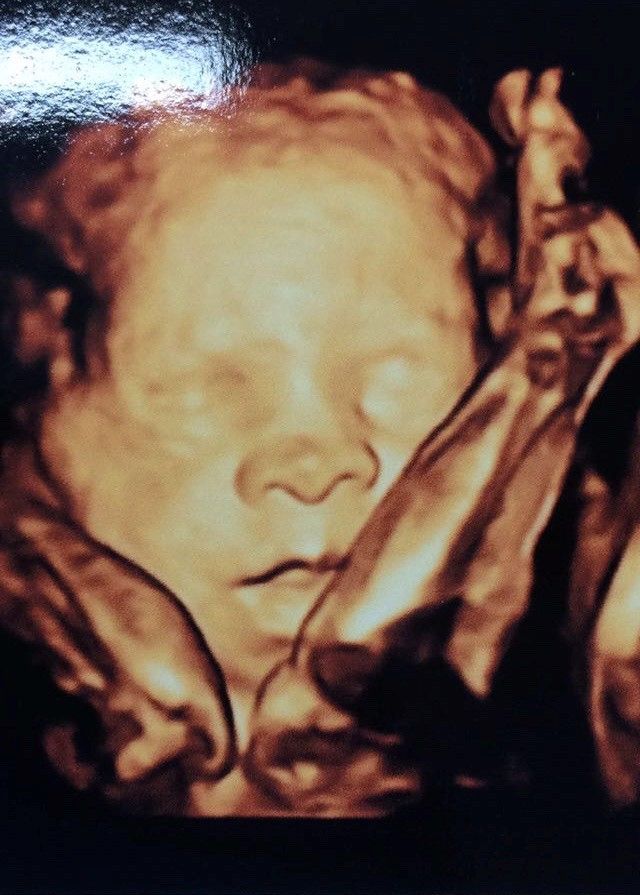

Fotos y videos